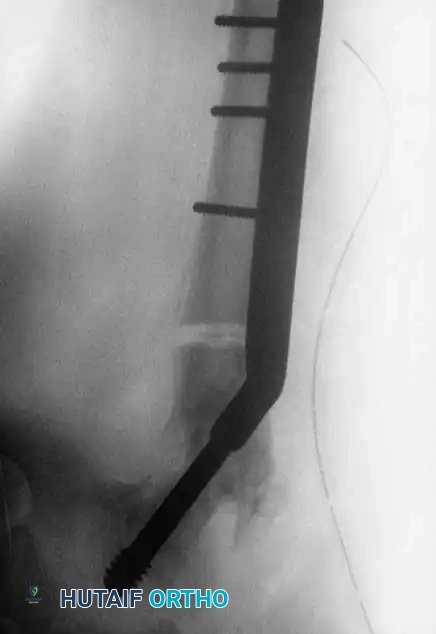

Fig. 15: Intraoperative reduction of the Type III fracture.

Fig. 16: Final fixation utilizing a cannulated screw and attached side plate to neutralize shear forces.